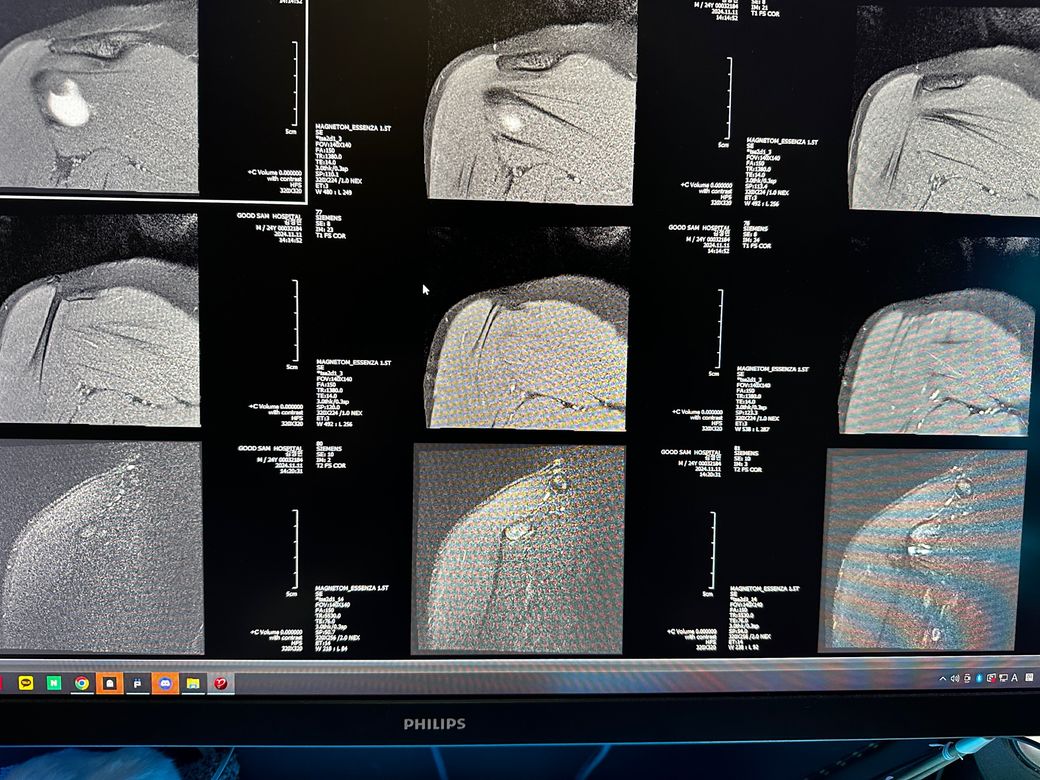

오른쪽어깨 관절mri좀 봐주세요 사진첨부입니다

오룬쪽어깨관절 엠알아이 결과좀 봐주세요

오른쪽어깨관절부분입니다

관절입니다

• 7번 째 사진

• 8번 째 사진

• 9번 째 사진

조영제가 들어간 것으로 보이며, "회전근개(특히 극상근) 파열이나 큰 손상은 뚜렷하게 보이지 않는 편"입니다.

관절와순(Labrum) 주변에 조영제가 퍼져 보이지만, "명확한 파열 소견은 사진만으로 단정 어렵고 경미한 손상.염증 가능성"은 있습니다.

관절 안쪽에 "약한 염증/활액 증가"는 있어 보이며, 충돌증후군 초기 형태 가능성이 있습니다.